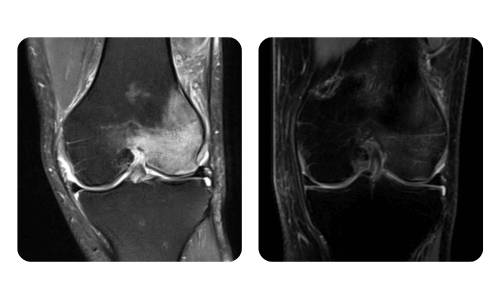

I progressi dei nostri pazienti, misurati prima e dopo la terapia iperbarica, riflettono l'efficacia e l'impatto positivo del trattamento. Scopri i risultati documentati della terapia iperbarica presso la clinica Hyperbarium Oradea, basati su valutazioni cliniche e dati oggettivi che evidenziano miglioramenti significativi in diverse condizioni.